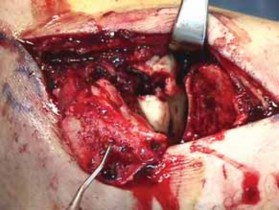

After completing the lateral approach, the surgeon carefully evaluates the lateral process fracture ( TECH FIG 5A,B).

1.

I gently displace the fracture and assess the condition of the subtalar joint.

2.

Small fragments are commonly devoid of soft tissue attachments. Only very small fragments should be removed.

3.

Larger fragments, even those without soft tissue attachments, are needed to restore the structure of the lateral process in any closed fracture of the lateral process of the talus.

40.

Any anterior or posterior osteochondral fragments are reduced and provisionally fixed with small, smooth Kirschner wires.

A Freer elevator is helpful to determine the anatomic subtalar joint line.

Final reduction of the direct lateral fragments of the lateral process is provisionally fixed by Kirschner wires.

41.

Isolated lateral process fractures are best fixed by interfragmentary mini-screw fixation.

42.

Comminuted fractures should be buttressed by mini-screw and plate fixation to resist displacement against axial loads to the process ( TECH FIG 5C,D).

---

A B C

TECH FIG 5 • Lateral process fracture of talus. A. Preoperative CT image. B. Intraoperative view of fracture. C. Intraoperative view of fixation. D D. Postoperative image. #### EXTERNAL FIXATION